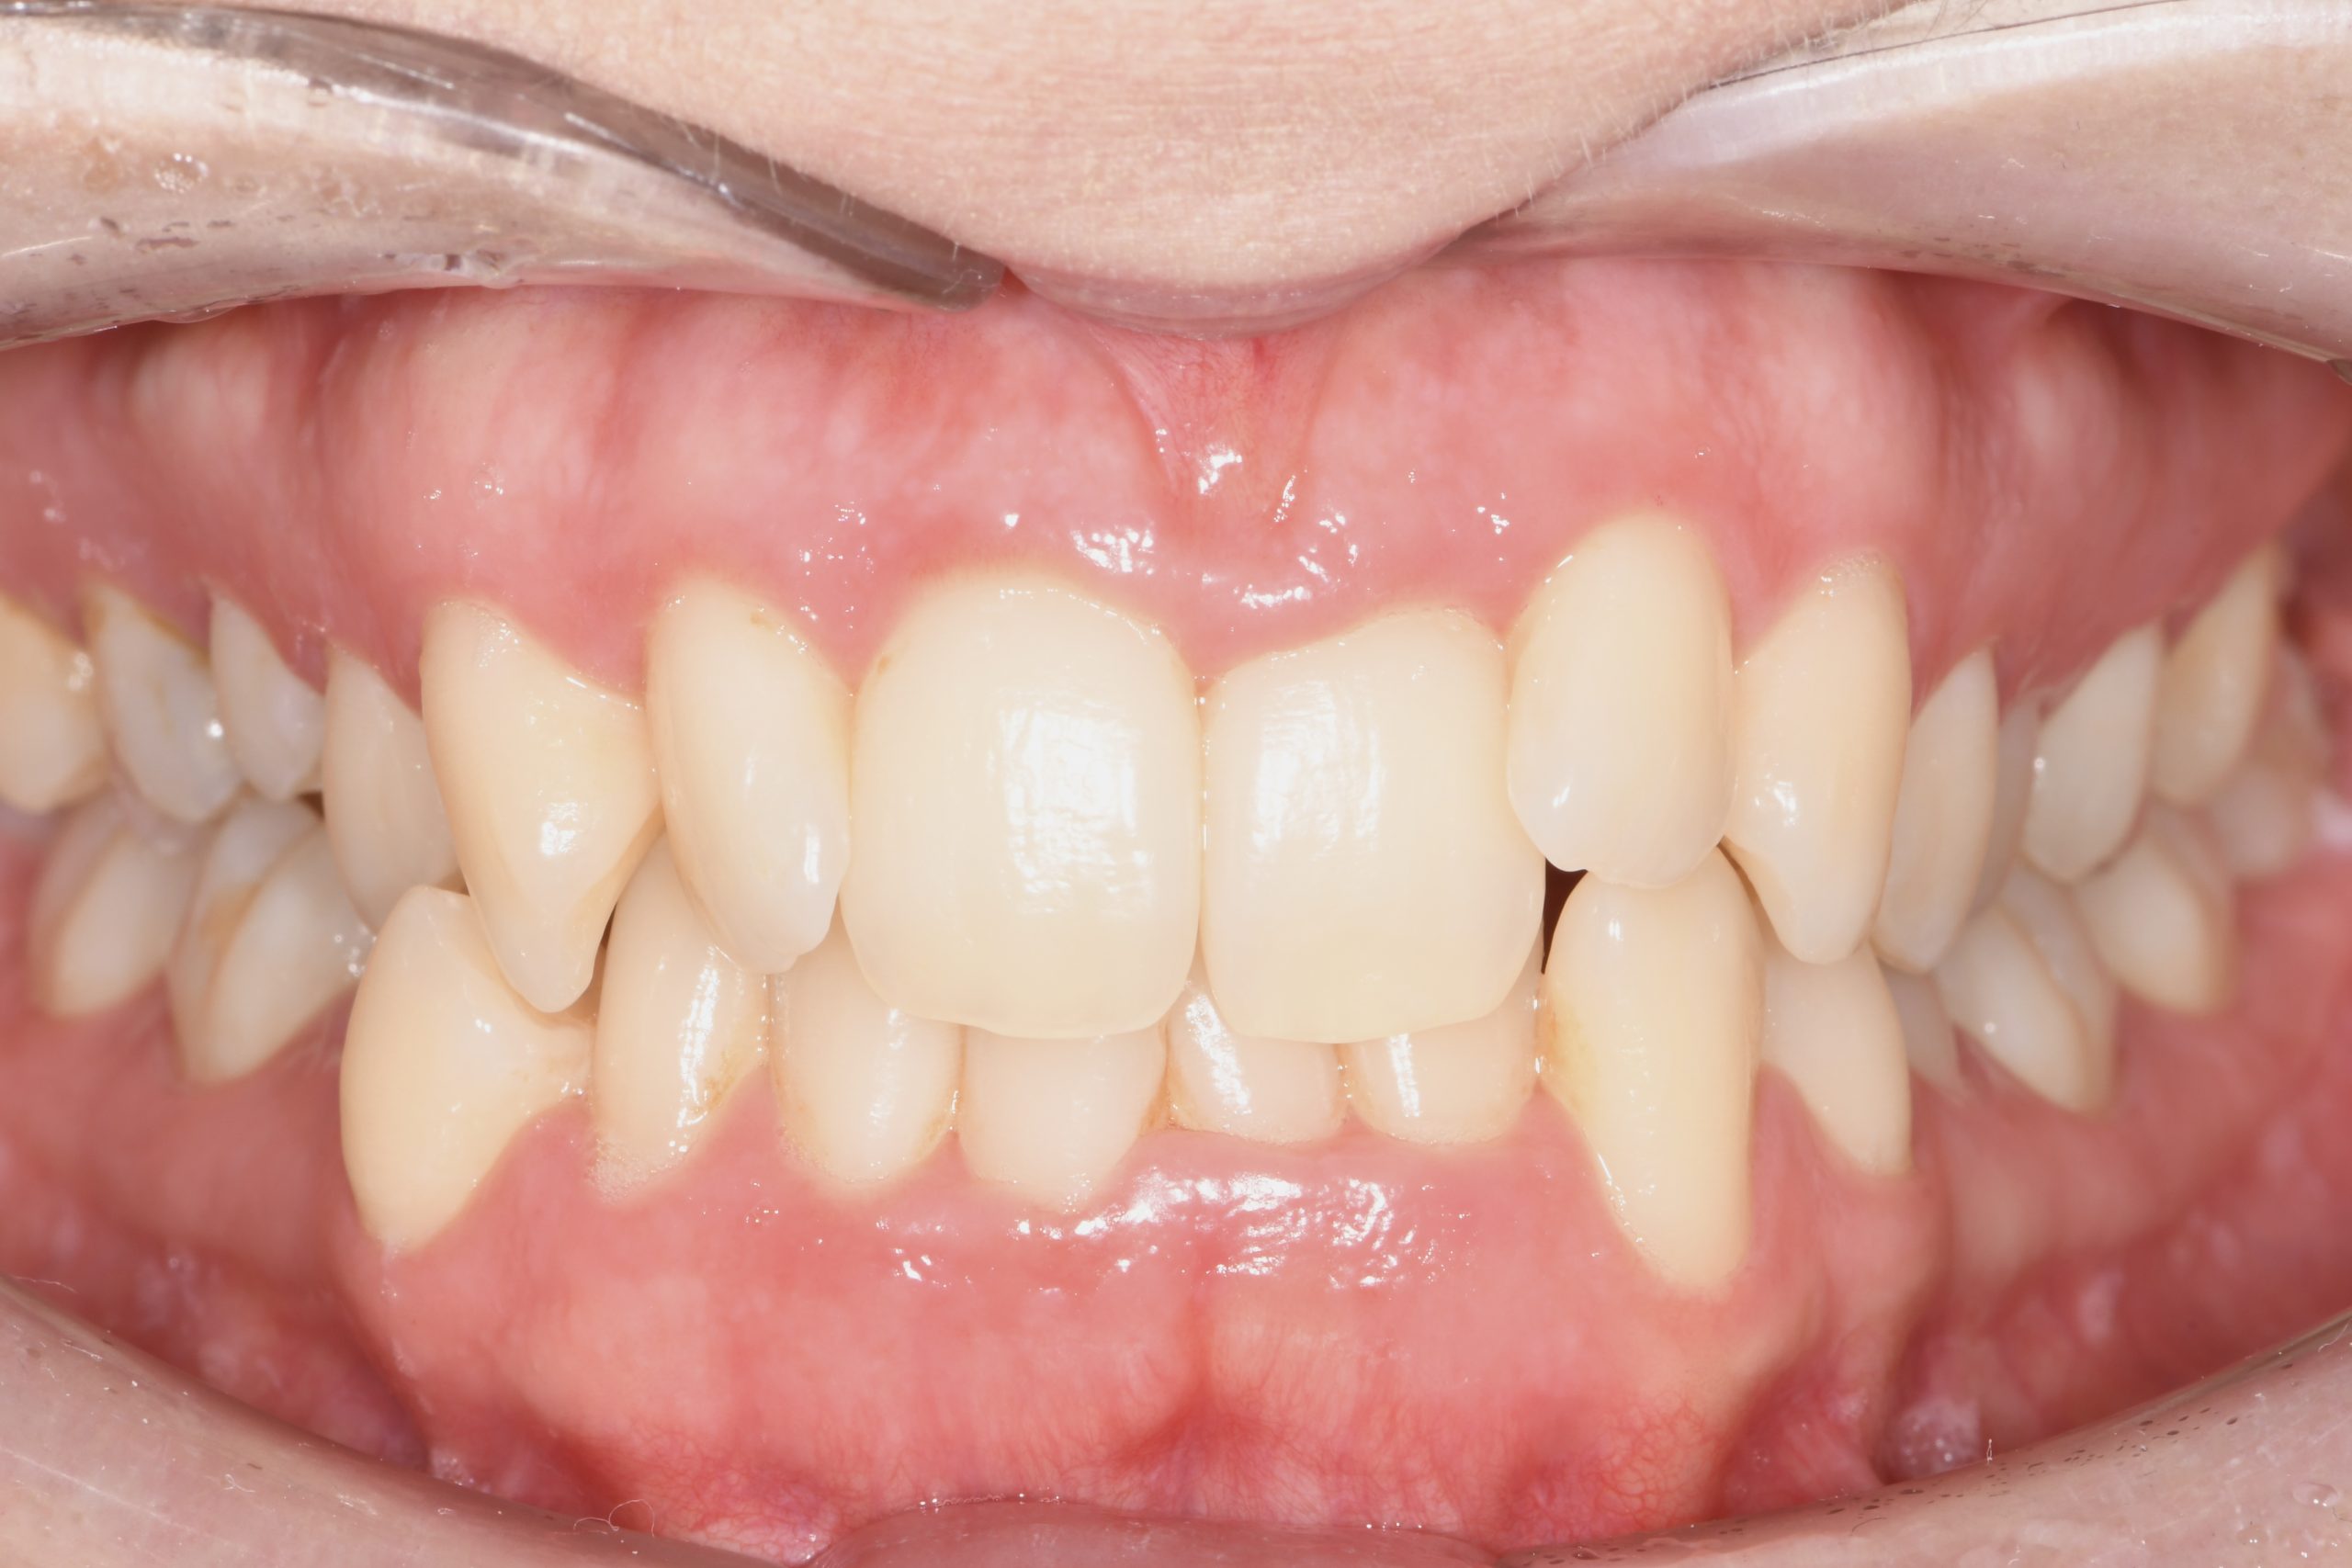

Az elmúlt évekből rengeteg szakmai referenciát tudnánk bemutatni, amelyek különböző fogszabályozási problémákat oldottak meg. Válogatva a több száz esetből, ezen az oldalon olyan képeket, információkat igyekeztünk bemutatni, amelyeknek a segítségével a jövőbeni pácienseinknek azt tudjuk üzenni: A Te fogsorod is lehet gyönyörű!

(Képeket a Pácienseink külön írásos beleegyezésével mutatjuk be!)